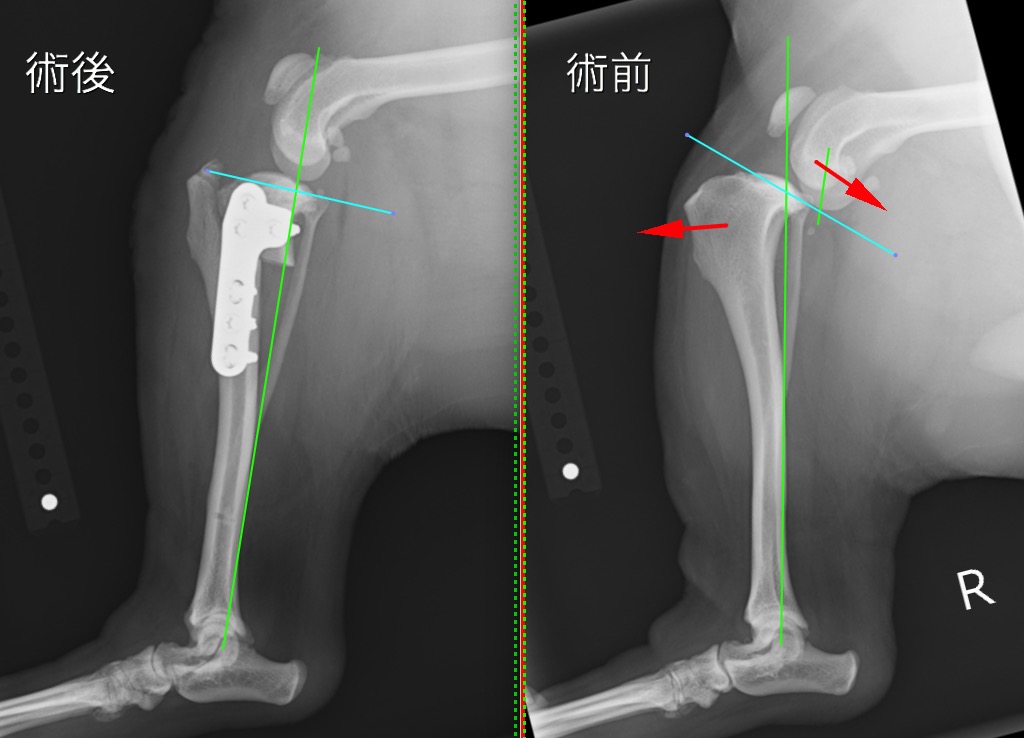

手術前後のX線写真を比較すると、術後は体重のかかる機能軸(緑線)に対して膝の中の傾斜(水色線)が垂直に近くなり、大腿骨と脛骨の連続性が回復しているのが分かります。

術後の経過は良好ではあり、術後1週間で退院、2週間で抜糸を行いました。